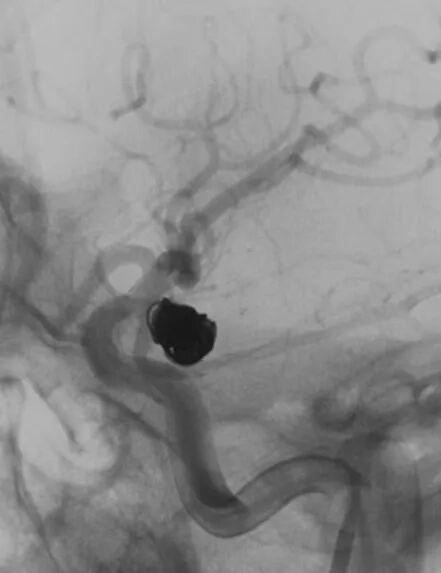

女,73岁,蛛网膜下腔出血量还挺多的,H-H 分级4级

造影显示左侧后交通动脉瘤

椎动脉造影没发现大脑后动脉,双侧的大脑后动脉都是由颈内动脉-后交通动脉发出,双侧胚胎型大脑后动脉